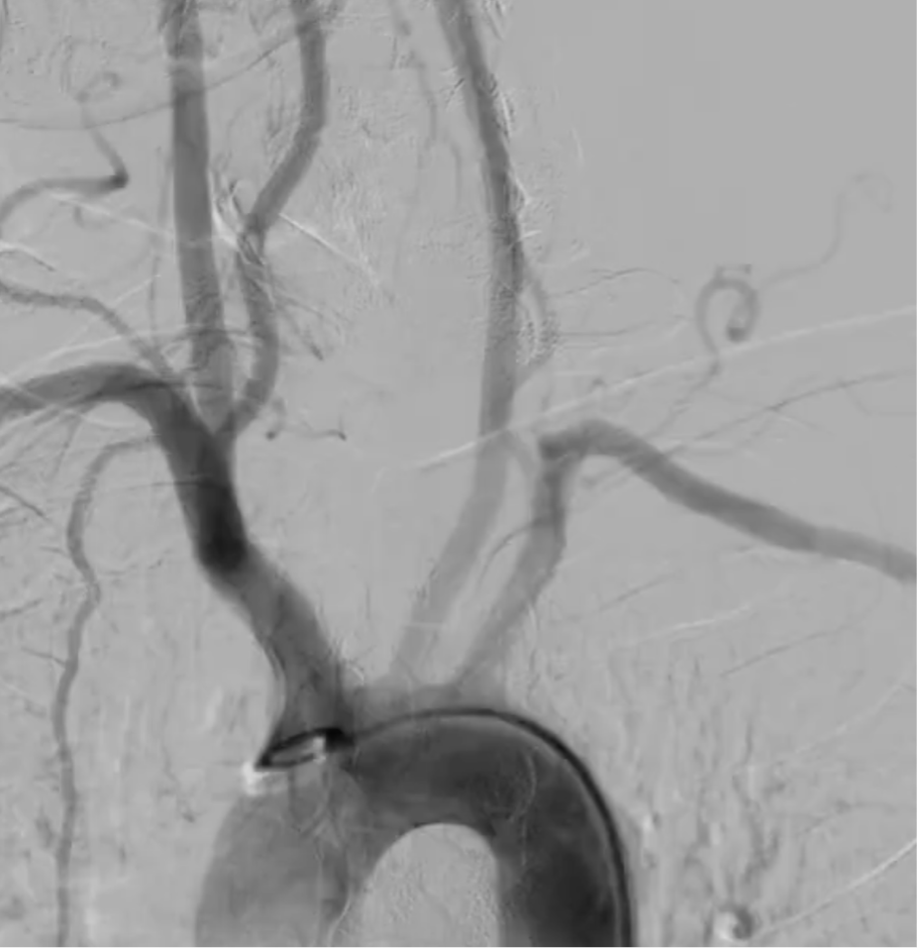

The lesion was crossed using a 0.014-inch guidewire via a retrograde approach from the left subclavian artery. An intravascular ultrasound (IVUS) catheter was advanced, and IVUS evaluation revealed a fibrolipidic plaque with a dominant fibrotic component. The minimal lumen area (MLA) measured 4.01 mm©÷, and the lesion length was 28 mm. The distal vessel diameter ranged from 7.63 to 8.06 mm. Slow and gradual predilation was performed using a 4.0 x 60 mm non-compliant balloon at the proximal segment of the subclavian artery. Subsequent IVUS evaluation demonstrated an eccentric plaque with limited plaque dissection, without evidence of medial dissection or intramural hematoma (IMH). The post-dilation MLA was 22.35 mm©÷ with a diameter of 5.06–5.63 mm. A 7.0 x 60 mm drug-coated balloon (low-dose paclitaxel) was then inflated at the proximal subclavian artery for 180 seconds. Final angiographic evaluation showed minimal residual stenosis without evidence of vessel perforation or dissection. The left vertebral artery remained patent with antegrade flow. No significant pressure gradient was noted between the aorta and the left subclavian artery. At six-month angiographic follow-up, the left subclavian artery remained patent with good antegrade flow.

This case illustrates the successful IVUS-guided drug-coated balloon angioplasty in treating subclavian steal syndrome caused by total occlusion of the proximal left subclavian artery. IVUS provided precise lesion characterization, accurate vessel sizing, and ensured optimal plaque modification. The use of a drug-coated balloon enabled effective luminal gain while minimizing restenosis risk without the need for stent implantation. The procedure achieved full vessel recanalization without complications. At six-month follow-up, angiography confirmed sustained patency, highlighting the safety and long-term efficacy of this endovascular approach.